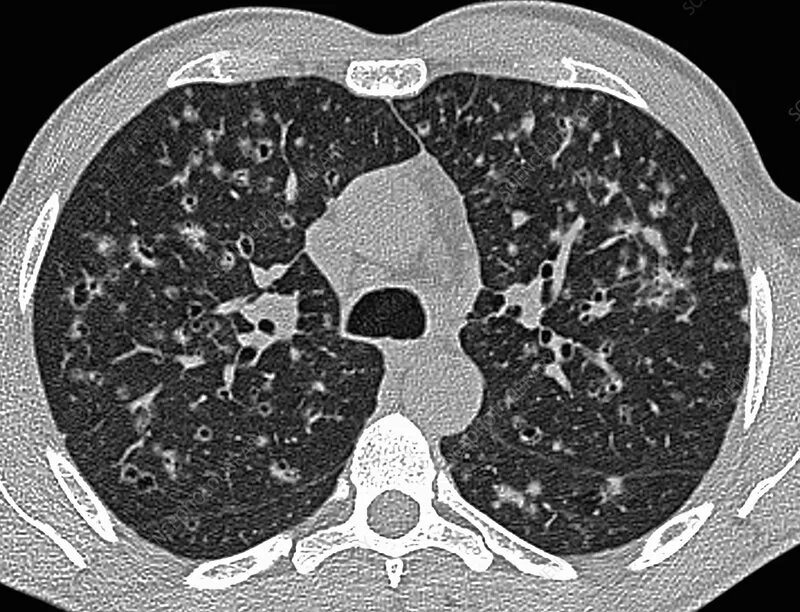

Кт х